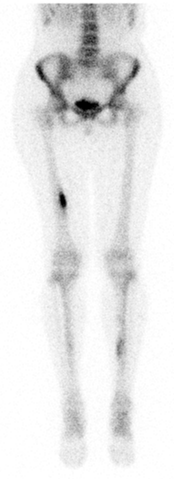

Сканирование костей

2. Остеосцинтиграфия